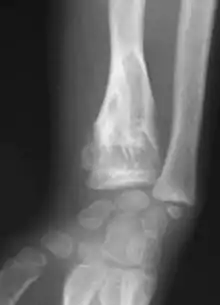

X-ray showing calcified enchondromas localized in finger a 37-year-old patient affected with Ollier disease

X-ray showing enchondromas localized in the humerus of a 37-year-old patient affected with Ollier disease

X-ray showing enchondromas localized in the lower part of the radius of a 37-year-old patient affected with Ollier disease